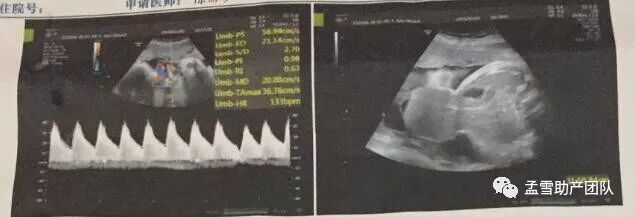

孟雪助产团队进驻田东中医院第五十七天。 今天专家门诊可谓是案例非凡。首先是一个二胎妈妈,41岁,36周,第一个宝宝12岁。在28周的时候诊断为脐膨出,妈妈告诉我们,当时是想打掉这个孩子,当我们一家人在讨论放弃的时候,宝宝动的非常频繁,搞得我浑身难受。我心里不是滋味,我感觉宝宝是有灵性的,有感知的。

当我说决定将他留下来的时候,宝宝又平静了,我的身体也随之舒服了。回想起做B超的时候,医生说宝宝卷缩着身体腹部看不清楚,医生让我活动了好久,几次都看不清楚,我想一定是宝宝不让医生看到自己的肚子上的缺陷,因此一整天都没有看清楚。